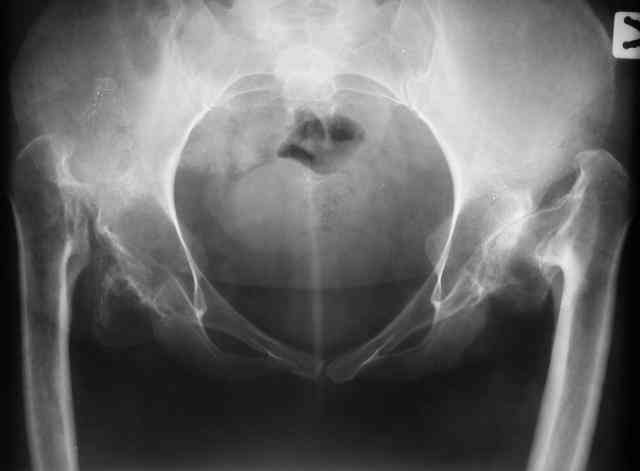

Уважаемые коллеги!В клинику обратилась больная 30 лет с жалобами на боль в области тазобедренных суставов (больше справа), ограничение движений в них.

Дисплазия была выявлена в 3-летнем возрасте, от операции родители тогда отказались. Около года назад при подъеме с кресла почувствовала резкую боль и хруст в правом бедре. С тех пор ходит только с ходунками.Выражены сгибательно-приводящие контрактуры. Справа - положительный симптом прилипшей пятки.

Мы планируем двустороннее тотальное бесцементное эндопротезирование. Первый этап - правый сустав. Чашку планируем имплантировать на свое анатомическое место, для чего резецируем часть бедренной кости. Смущают сильный остеопороз в области впадины и кривизна бедра...Ваши комментарии?-- С уважением,А. В. Вакуленко